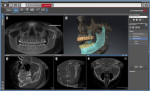

B | Implant Studio

Figure 2 | Implant Studio® is perfect for prosthetic driven implant planning and surgical guide design. It offers accuracy and predictability, while improving the patient’s experience and supports a range of implant treatments. This software integrates with a wide range of 3D printers and milling machines.

908-867-0144

3shape.com